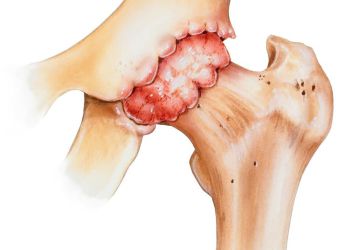

• Коксартроз — артроз тазобедренного сустава. Данная разновидность заболевания является лидирующей.